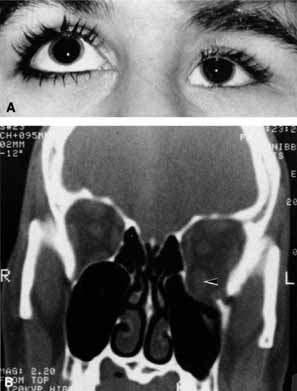

Pseudoproptosis may be caused by ophthalmoparesis, in which the lax muscles allow the globe to prolapse forward. Proptosis should be of minimal degree and the globe is easily reducible. High myopia, contralateral enophthalmos (see Fig. 26), orbital asymmetry, blepharoptosis, or eyelid retraction can also produce pseudoproptosis.11 CASE 6 A 40-year-old man developed severe, unrelenting, right-sided headache 1 month after falling from a roof. He noted ptosis and a small pupil coincident with onset of the headache (Fig. 27A). The arteriogram disclosed a narrowed internal carotid artery compatible with the diagnosis of a carotid artery dissection (Fig. 27B). An example of referred pain and Horner's syndrome is the carotid artery dissection syndrome.49 When the dissection occurs the patient generally develops unilateral referred orbital pain, ptosis, and a miotic pupil but without anhidrosis (see Fig. 27A). Typically, dissection occurs in the older, vasculopathic patient or days to weeks after head trauma. The symptoms are similar to those of cluster headache, that is, recurrent unilateral severe headache and oculosympathetic paresis, the difference in carotid artery dissection being unrelenting pain and unresponsiveness to normal migraine therapy. Arteriogram or magnetic resonance imaging are useful for documentation of the carotid artery dissection (see Fig. 27B). |